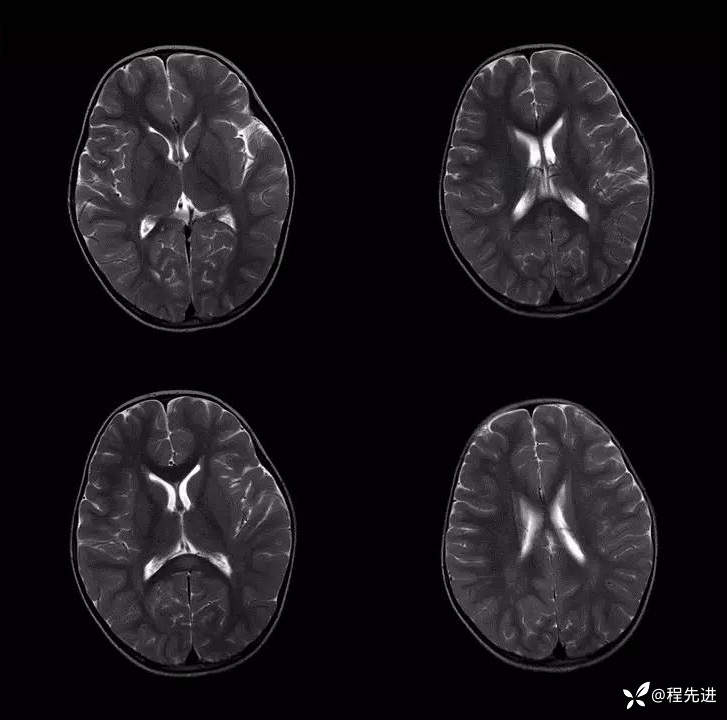

患者性别:女

患者年龄:3岁

主诉:间断呕吐2天,伴腹泻1天,惊厥1次

现病史:2天前进食后呕吐,非喷射状,1天前出现腹泻,每日4-5次。入院2小时前出现抽搐发作

辅助检查:便常规轮状病毒(+)

伴可逆性胼胝体压部病变的轻度脑炎 (7)